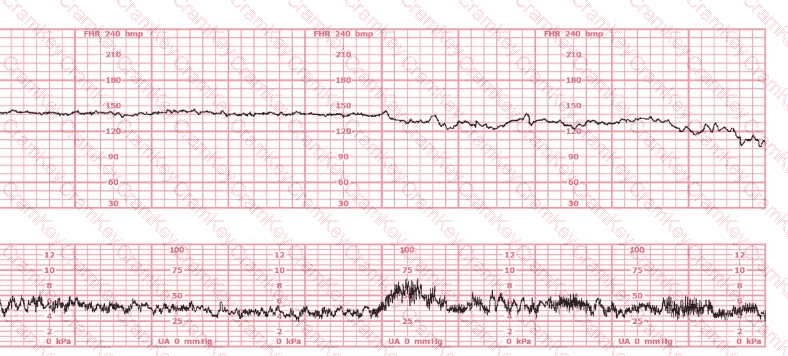

This external tracing is from a 19-year-old (G1P0) at 39-weeks gestation. She is 6 cm dilated, 100% effaced, and –2 station. The fetus is in an occiput posterior position. She rates her pain as 8. She reports being lightheaded. She is most likely at risk for respiratory: